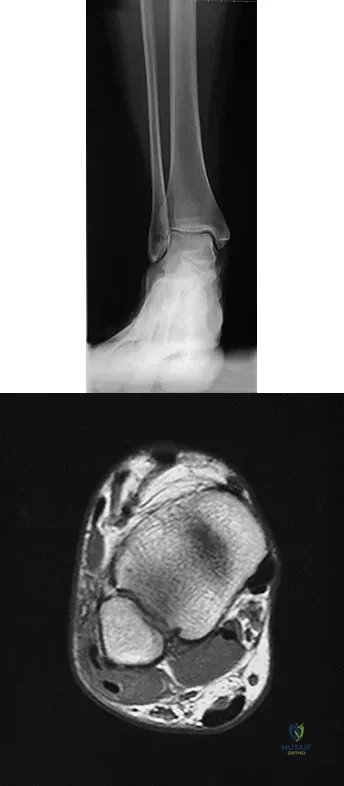

A 15-year-old girl reports a 6-month history of activity-related knee pain and swelling. A radiograph, MRI scan, and biopsy specimen are shown in Figures 21a through 21c. What is the most likely diagnosis?

The epiphyseal location on the radiograph and MRI scan and the histologic findings of polyhedral cells separated by a chondroid matrix with pericellular, lattice-like "chicken wire" calcification all suggest chondroblastoma. Although giant cell tumors of bone typically occupy an epiphyseal location, they are rare in children and when present are often metaphyseal in skeletally immature patients. Enchondromas and osteoblastomas are generally metaphyseal and, along with giant cell tumors, have very different histology than seen here. Chondromyxoid fibromas are typically metaphyseal in location. Huvos AG: Bone Tumors: Diagnosis, Treatment, and Prognosis. Philadelphia, PA, WB Saunders, 1991, pp 295-313.